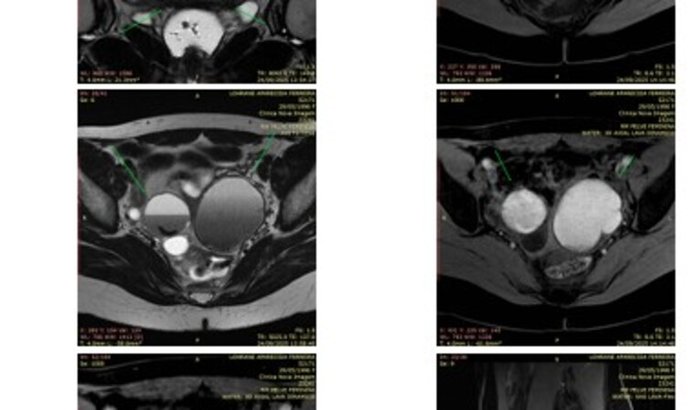

O caso dela é urgente: o tecido da endometriose já se espalhou, afetando os ovários, e ela possui um cisto no ovário esquerdo medindo 6 cm. Recentemente, ela começou a sentir dor na perna esquerda, e ter dificuldades para andar, suspeitamos que está atingindo a região do nervo ciático. Essa condição está trazendo riscos reais para sua saúde e mobilidade.

Os dias da Lohrane são marcados por limitações. Ela mal consegue andar devido a dor na perna esquerda que começou, sente dores na relação. O diagnóstico é claro: a única maneira de curá-la e devolver sua qualidade de vida é através de uma cirurgia especializada e de alta precisão.